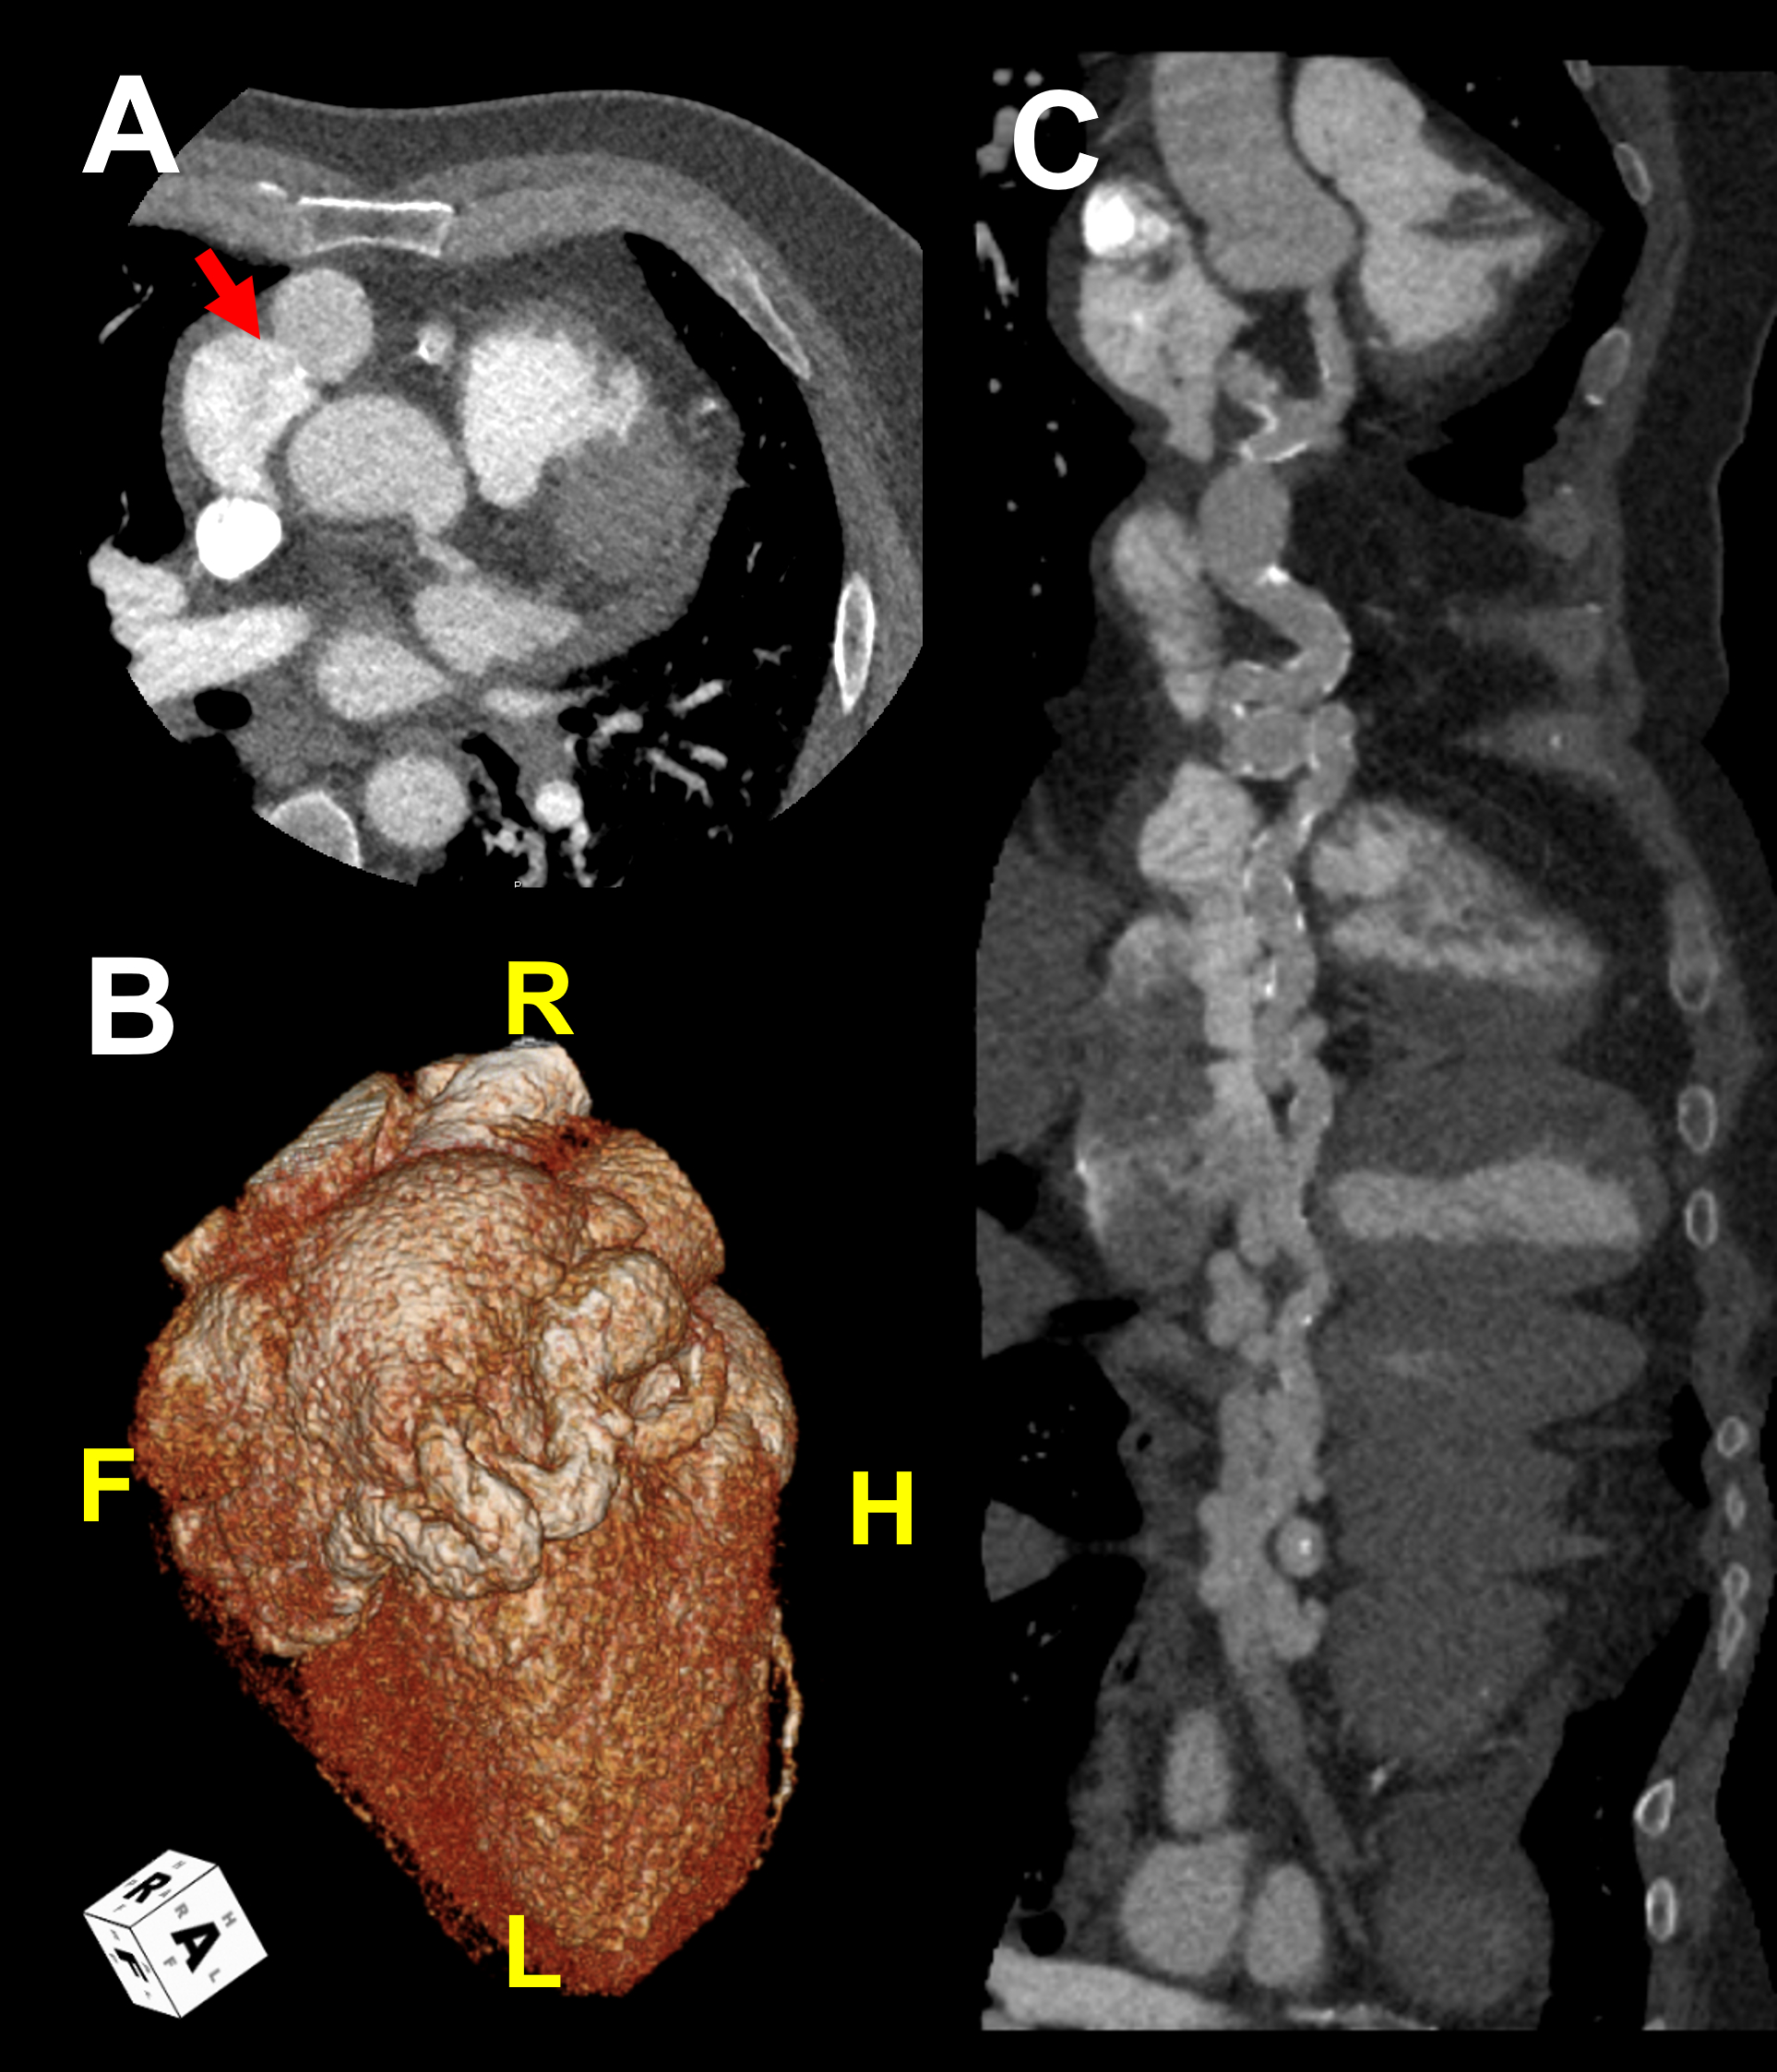

Echocardiography showed reduced LVEF of 30%, and cardiac catheterization found hemodynamically significant shunt with Qp:Qs of 1.47:1. Coronary angiography revealed a tortuous and extremely aneurysmal RCA, as well as multivessel coronary artery disease (mvCAD) involving LAD, D1, LCx, OM1. Notably, the LAD had multiple aneurysmal segments and areas of eccentric stenosis upto 90%.

Multislice CT angiography further characterized the RCA, which extends to the coronary sinus (CS) distally forming a coronary cameral fistula (CCF). Cardiac MRI did not show significant ischemic findings.